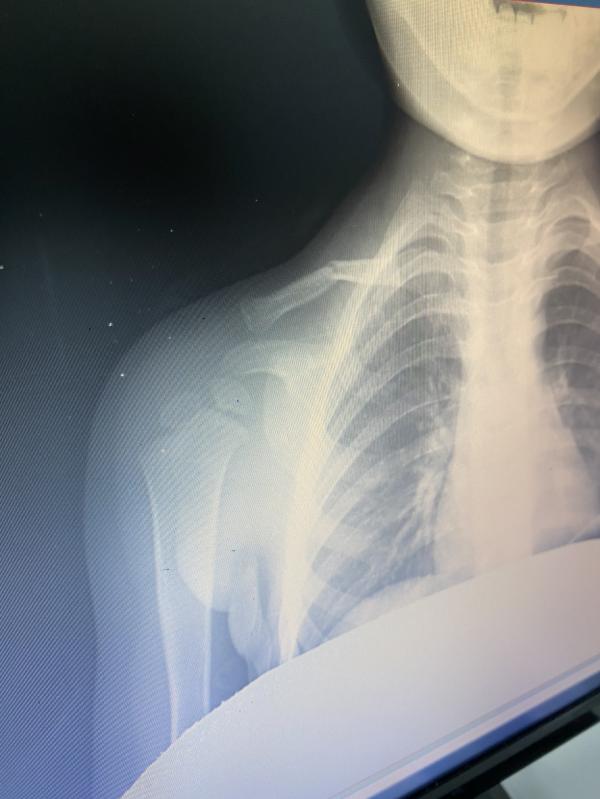

Подскажите пожалуйста, сын поломал ключицу 29 декабря. Теперь нам нужна повязка дезо или дельбе. Может у кого нибудь дома лежит? Ребенку 2 года. Я куплю. Помогите вывести в топ 🙏🏻 чтобы увидели большинство💐💐